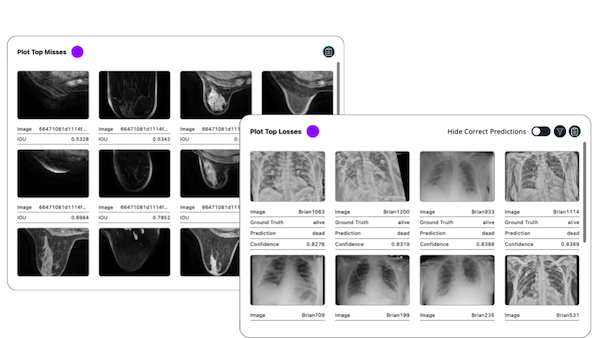

While the FDA has its own guidelines for clinical AI performance testing, there is no industry standard platform for doctors or developers to use on their own. Gesund.ai has spent years creating a clinical AI validation software suite now used across different healthcare settings. It encompasses many different FDA-aligned feature sets relevant for real-world deployment. Now, the company is opening up the library of methodologies and frameworks used in combination with its validation engine for anyone to use, update and edit.

Called Gesund Validate, Healthcare, AI and industry professionals can access it at this link. Validate is open source and has many benefits for AI developers and healthcare providers, like:

- Covers the clinical AI solutions physicians use, like radiology, because it is built on unstructured multimodal data adopting “expert-in-the-loop” workflows and a wide range of computer vision tasks.

- Spots bias by analyzing model performance across patient metadata like age, gender, and race against built-in fairness and bias mitigation methodologies.